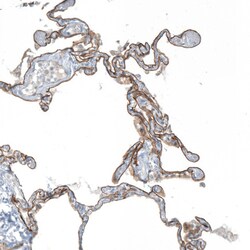

Invitrogen™ Agrin Polyclonal Antibody

Brand: Invitrogen™ PA559064

| Immunohistochemistry (Paraffin), Immunocytochemistry | |